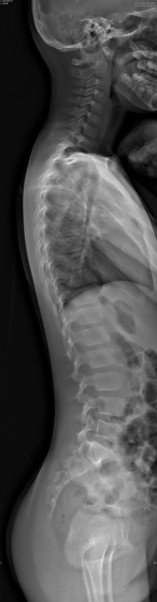

Adolescent spines undergo rapid growth and hormonal changes, making them prone to scoliosis, hyperkyphosis, and back pain.

Monitoring during puberty is vital, as spinal curves can progress quickly and impact posture, function, and long-term musculoskeletal health.

The adult spines, fully matured, supports mobility and daily function.

Trauma, degeneration, inflammation, and repetitive strain can disrupt biomechanics, causing pain and reduced flexibility.

The aging spines undergo disc dehydration, bone loss, and joint degeneration.

These changes increase the risk of joint pain, fractures, and deformity.